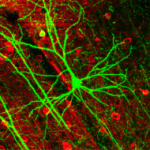

Después de inyectar proteína verde fluorescente en las células precursoras de neuronas en embriones de ratones con una vida media de 18 meses, Lorenzo Magrassi de la Universidad de Pavia y su equipo trasplantaron las células en los fetos de ratas Wistar, que viven el doble de tiempo. Una vez que las células se habían diferenciado, los investigadores se centraron en un tipo de neurona se llama una célula de Purkinje (PC).

Los ratones pierden casi la mitad de sus neuronas mucho antes de que lleguen a la vejez. Se utilizaron ratas Wistar, por otro lado, porque estas pueden mantener casi la totalidad de sus PC hasta que mueren. Los investigadores sacrificaron las ratas después de tres años. Cuando examinaron los cerebros de las ratas, encontraron que los PCs trasplantadas sobrevivieron hasta en los animales muertos. Las neuronas mostraran los mismos signos de envejecimiento como las neuronas de las otras ratas.

Aunque Magrassi y sus colegas fueron capaces de aumentar la vida útil de las neuronas trasplantadas de manera significativa, el trasplante no alteró todas las características de las neuronas. Los PCs retenido el pequeño tamaño que normalmente se encuentran en los ratones. Magrassi dice que la investigación demuestra que la longevidad de las neuronas no está predeterminado.